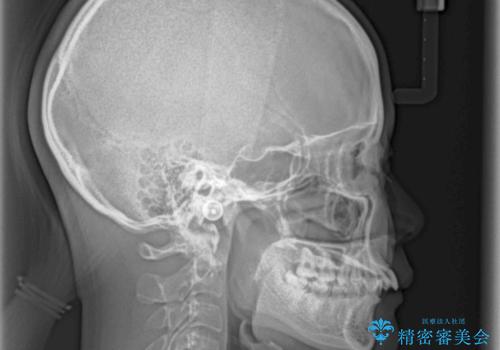

- 深い咬み合わせと上顎前歯の突出感を気にして来院された患者様です。

当院では通常、臼歯の咬合が理想的な位置に対して上顎が前方位にある場合。ワイヤー矯正または補助装置の併用したインビザライン矯正を選択しています。

正面や横からの写真ではきれいに治っており、患者様は大変満足のいく仕上がりとなりましたが、深い咬み合わせの改善は不十分で、奥歯の咬み合わせも改善させることができませんでした。